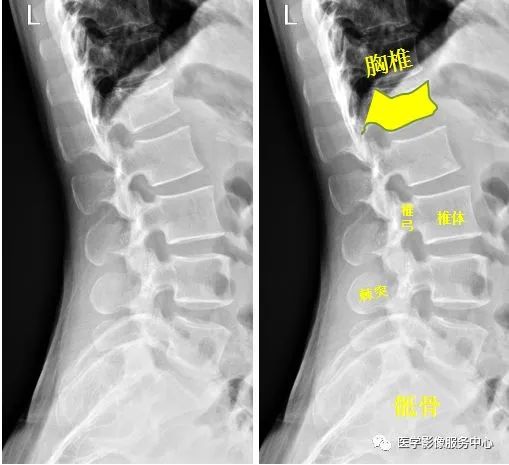

(七)脊柱

腰椎侧位示:第1腰椎呈前低后高楔形改变,腰椎第1椎体陈旧性压缩性骨折。

Warmreminder: 陈旧性骨折多在做其他检查时发现,压缩性骨折因受伤时重力向下所致,腰椎、胸椎易发生。

小妙招:此患者腰痛来院,询问病史,十年前从楼上坠落,休息一段时间后无大碍,并没有行检查。